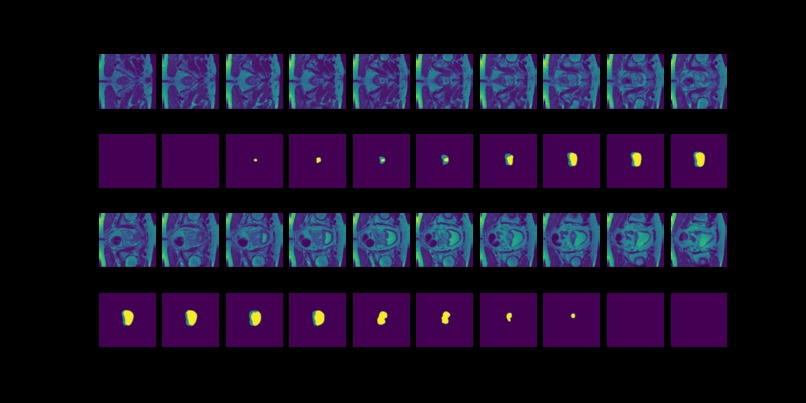

Figure 9: True (top) and predicted (bottom) segmentation from dilated FCN trained with data augmented by flipping and rotation.

Figure 10: True (top) and predicted (bottom) segmentation from DeConvNet trained with data augmented by flipping and rotation.

Figure 11: True (top) and predicted (bottom) segmentation from U-Net trainedwith data augmented by flipping and rotation.

FCN is outperformed by the two encoder-decoder models due to the thin deconvolutional layer as decoder and coarse output in the final deconvolutional layer. The dilated FCN managed to improve performance of FCN but is still outperformed by the encoder-decoder models. For the two encoder-decoder based models, U-Net outperforms DeConvNet in general. This is not surprising since U-Net is specifically designed for medical images and is supposed to achieve higher segmentation accuracy with fewer data. Moreover, randomly flipping input images seems to help improve performance for both of the models. Figure 8 and Figure 9 are the true (top) and predicted (bottom) segmentation of 10 test images from FCN and dilated FCN trained with data augmented by flipping and rotation. Figure 10 and Figure 11 are the true (top) and predicted (bottom) segmentation of 10 test images from DeConvNet and U-Net trained with data augmented by flipping and rotation. It can be seen that U-Net gives a smoother edge than FCN, dilated FCN and DeConvNet.